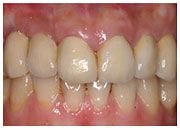

施小姐長相十分甜美,但是一直為小時候所做的門牙假牙不美觀所苦, 經過黃醫師為其訂立前牙美容美化的治療計畫後,以極其自然與美觀兼顧的全瓷冠人工植牙, 還給施小姐一個更美麗的笑容。

治療後